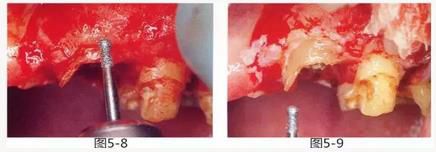

圖5-8,9

使用金剛砂車針削除牙根周圍的牙槽骨,從牙槽嵴頂露出至少3mm的健全牙體組織。